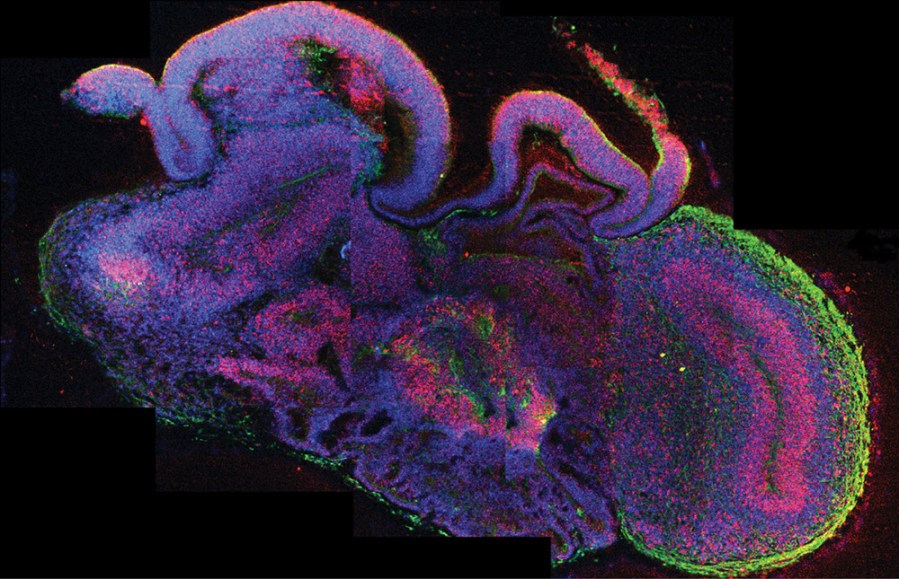

Not a squid. This lab-grown tissue has brainlike structures, including neurons (in green) and the stem cells that will make more neurons (here appearing red and purple).

Madeline A. Lancaster

After two months, the tissue had outgrown the gel droplet and now measured about 4 millimeters (0.16 inch) across. The scientists have already grown hundreds of these mini brainlike bits. And at this stage of development, the tissue’s stem cells have begun to mature into specialized cells called neurons. These are the primary cells that make up the brain. These neurons have even begun organizing into brain structures. One was the hippocampus, a center of memory and emotion. Another was the cerebral cortex, the outer layer of the brain. Experiments showed that some neurons were sending out signals, a sign of activity.